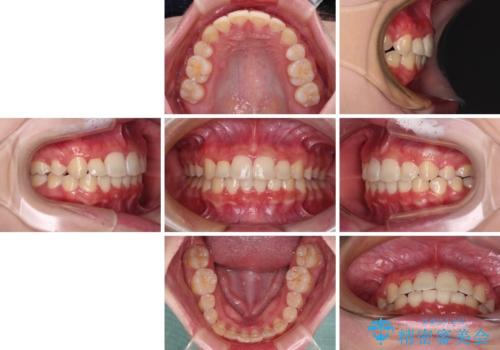

- 八重歯やデコボコをインビザラインで治療したいとのことで来院された患者様です。

インビザライン単体で治療を行うには叢生が強いと判断されたため、事前にワイヤー装置で抜歯矯正を行い、ある程度改善してからインビザラインにて仕上げていくこととしました。